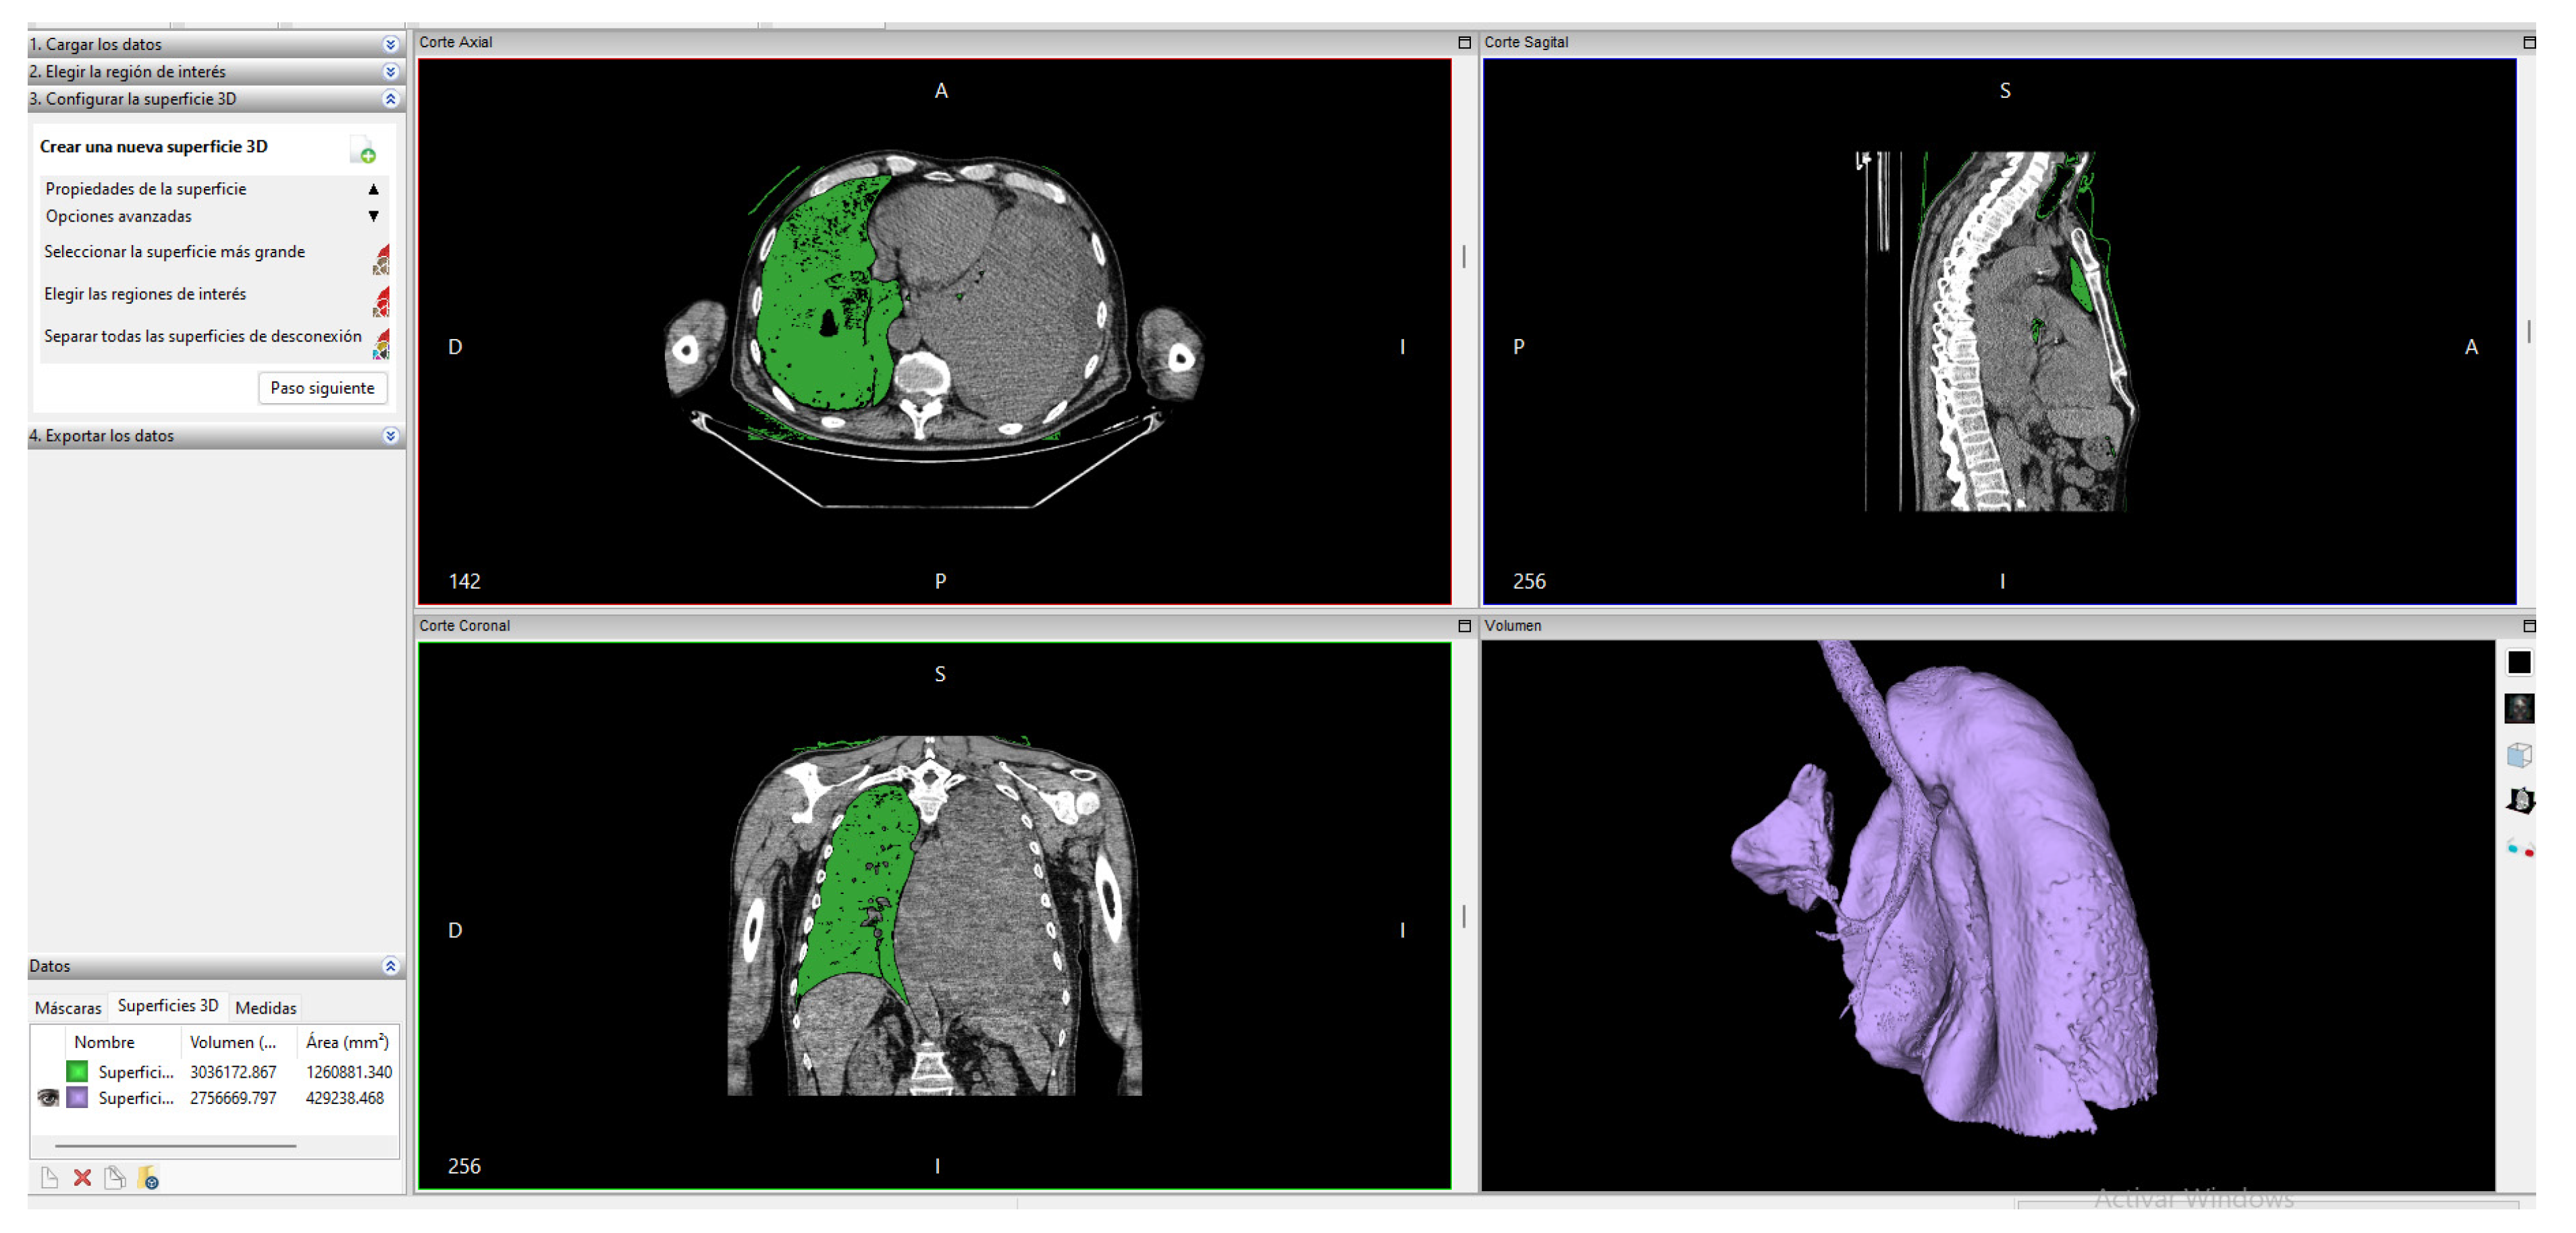

2.3.2. Invesalius

In this software, the process has a unique order of steps for segmentation; When the CT files are imported, a section of interest is cut with the “Cut” tool to create a mask by varying HU ranges depending on the tissue we want to segment. To segment this section, we must choose a threshold, and this software only allows us to visually choose the appropriate range of values for the segmentation. The values chosen can be seen in Figure 3.

Range of selected values.

Later, within the “advanced options” we have the option to select the largest surface of the created segment; with this, we obtain the final surface that can be seen in Figure 4.

Figure 4.

Lung segmentation in Invesalius.